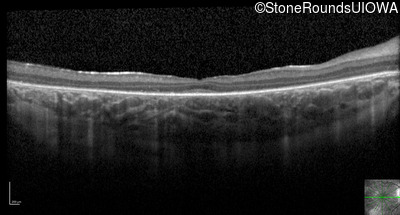

Optical Coherence Tomography - Left - 20/80

Exemplar / OCT Stack